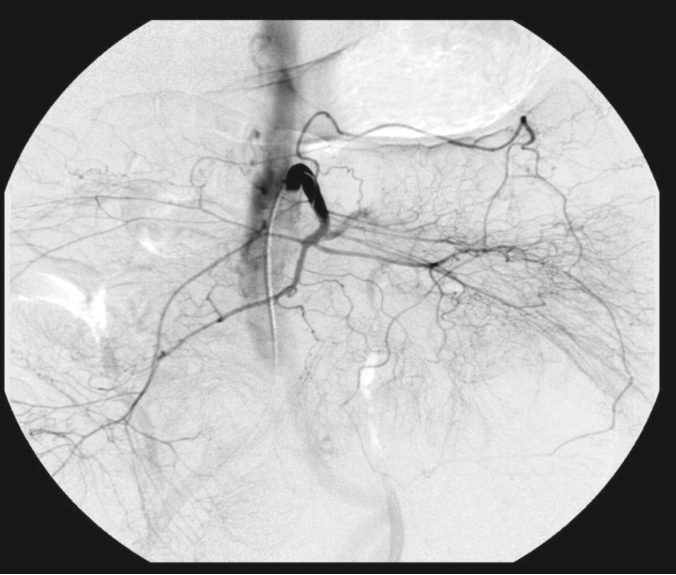

79岁 柏油样便,Hb急速下降;胃镜及结肠镜没能诊断;增强CT提示回肠造影剂外溢 ![]() SMA DSA (6ml/sec, 80ml) 微导管达不到理想的位置

微粒栓塞

术后生命体征开始稳定,但仍然间断出血,最终决定手术